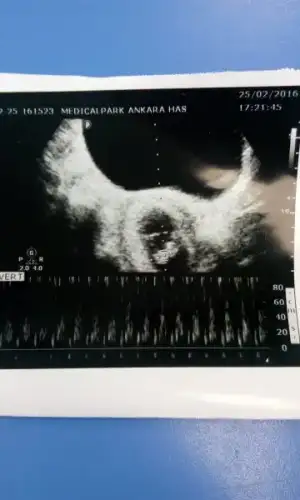

Bu da bugünkü foto

Hatta ense kalınlığı da iyi dedi doktor her şey normal dedi

Tatlım ok tam nubunun üstüne gelmiş ama bu da paralel gibi :) paralel olunca nub prenses oluyor :)